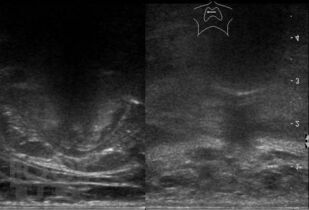

Ультразвуковое исследование оперированной щитовидной железы

В основу монографии положены материалы собственных исследований и практический опыт использования ультразвуковых методов диагностики при обследовании пациентов после хирургических вмешательств на щитовидной железе. Продемонстрированы диагностические возможности ультразвукового исследования в оценке состояния оперированной щитовидной железы в раннем и отдаленном послеоперационном периоде. Обобщена, систематизирована и представлена ультразвуковая семиотика зоны операции в ближайшие сроки после хирургических вмешательств и отражена динамика выявленных изменений. Убедительно показано, что ультразвуковое исследование может быть эффективным методом послеоперационного наблюдения.